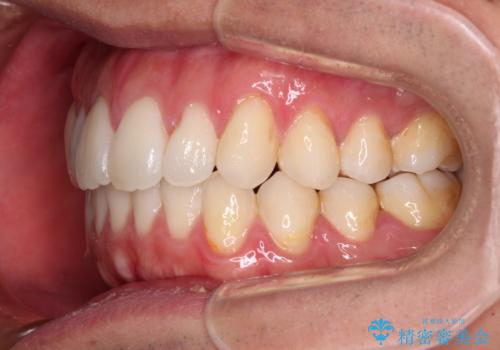

- 全体的なデコボコと、前歯の前に出ている感じを気にして来院された患者様です。

患者様と相談の上、非抜歯にてインビザラインを用いて矯正治療を行うこととし、IPR(歯と歯の間)並びに歯列全体の後方移動により口元の突出感の改善することとしました。

お仕事が忙しい方で、装着時間が不足したり、定期的な通院ができなかったりと、自己管理が重要なインビザラインによる矯正治療が長期化する要因が重なり、5年ほどの期間を要しました。